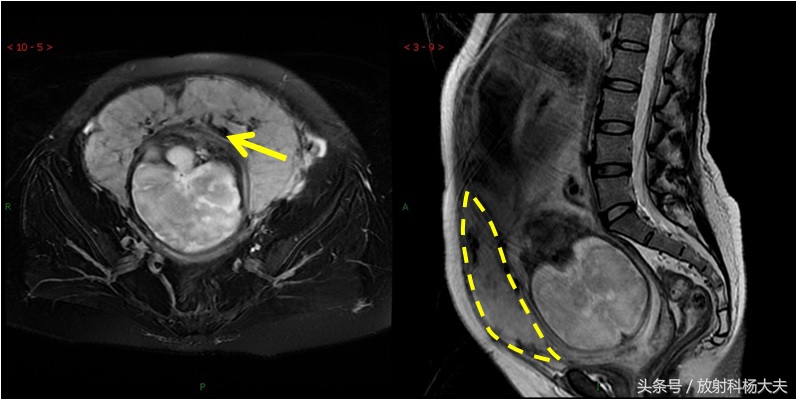

在MRI上显示植入部位子宫肌层局部均不同程度地变薄,胎盘基底面不规则。低信号的子宫肌层内见局部高信号病灶,呈结节状或三角形、锯齿状、不规则形,T2WI胎盘内信号不均匀,内可见较多、粗大的流空血管影和低信号带。严重时胎盘可穿过肌层,穿通部位肌层信号中断,胎盘基底面与子宫壁融合,分界不清。但请注意,目前的技术,MRI的诊断准确率也只能做到82%而已。

胎盘植入的MRI图。黄箭所示黑黑的东西就是一些粗大的血管,可以想象这些血管破裂会有多可怕的后果。另外出血的原因是胎盘植入到子宫壁内,难以剥离。